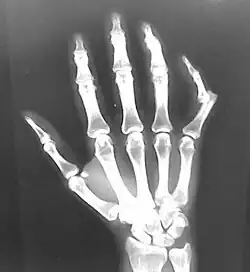

| Luxação no dedo indicador | |

Raios X geralmente são realizados para confirmar o diagnóstico e detectar qualquer fratura que possa ter ocorrido no momento da luxação. Uma luxação é facilmente vista em um raio-X.